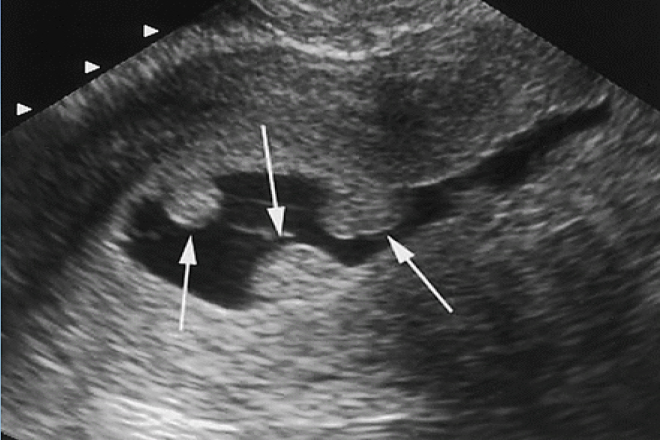

- Ecografía transvaginal

- Sonohisterografía

- Histeroscopía (método más preciso)

La histeroscopía permite ver el pólipo directamente y retirarlo en el mismo procedimiento.